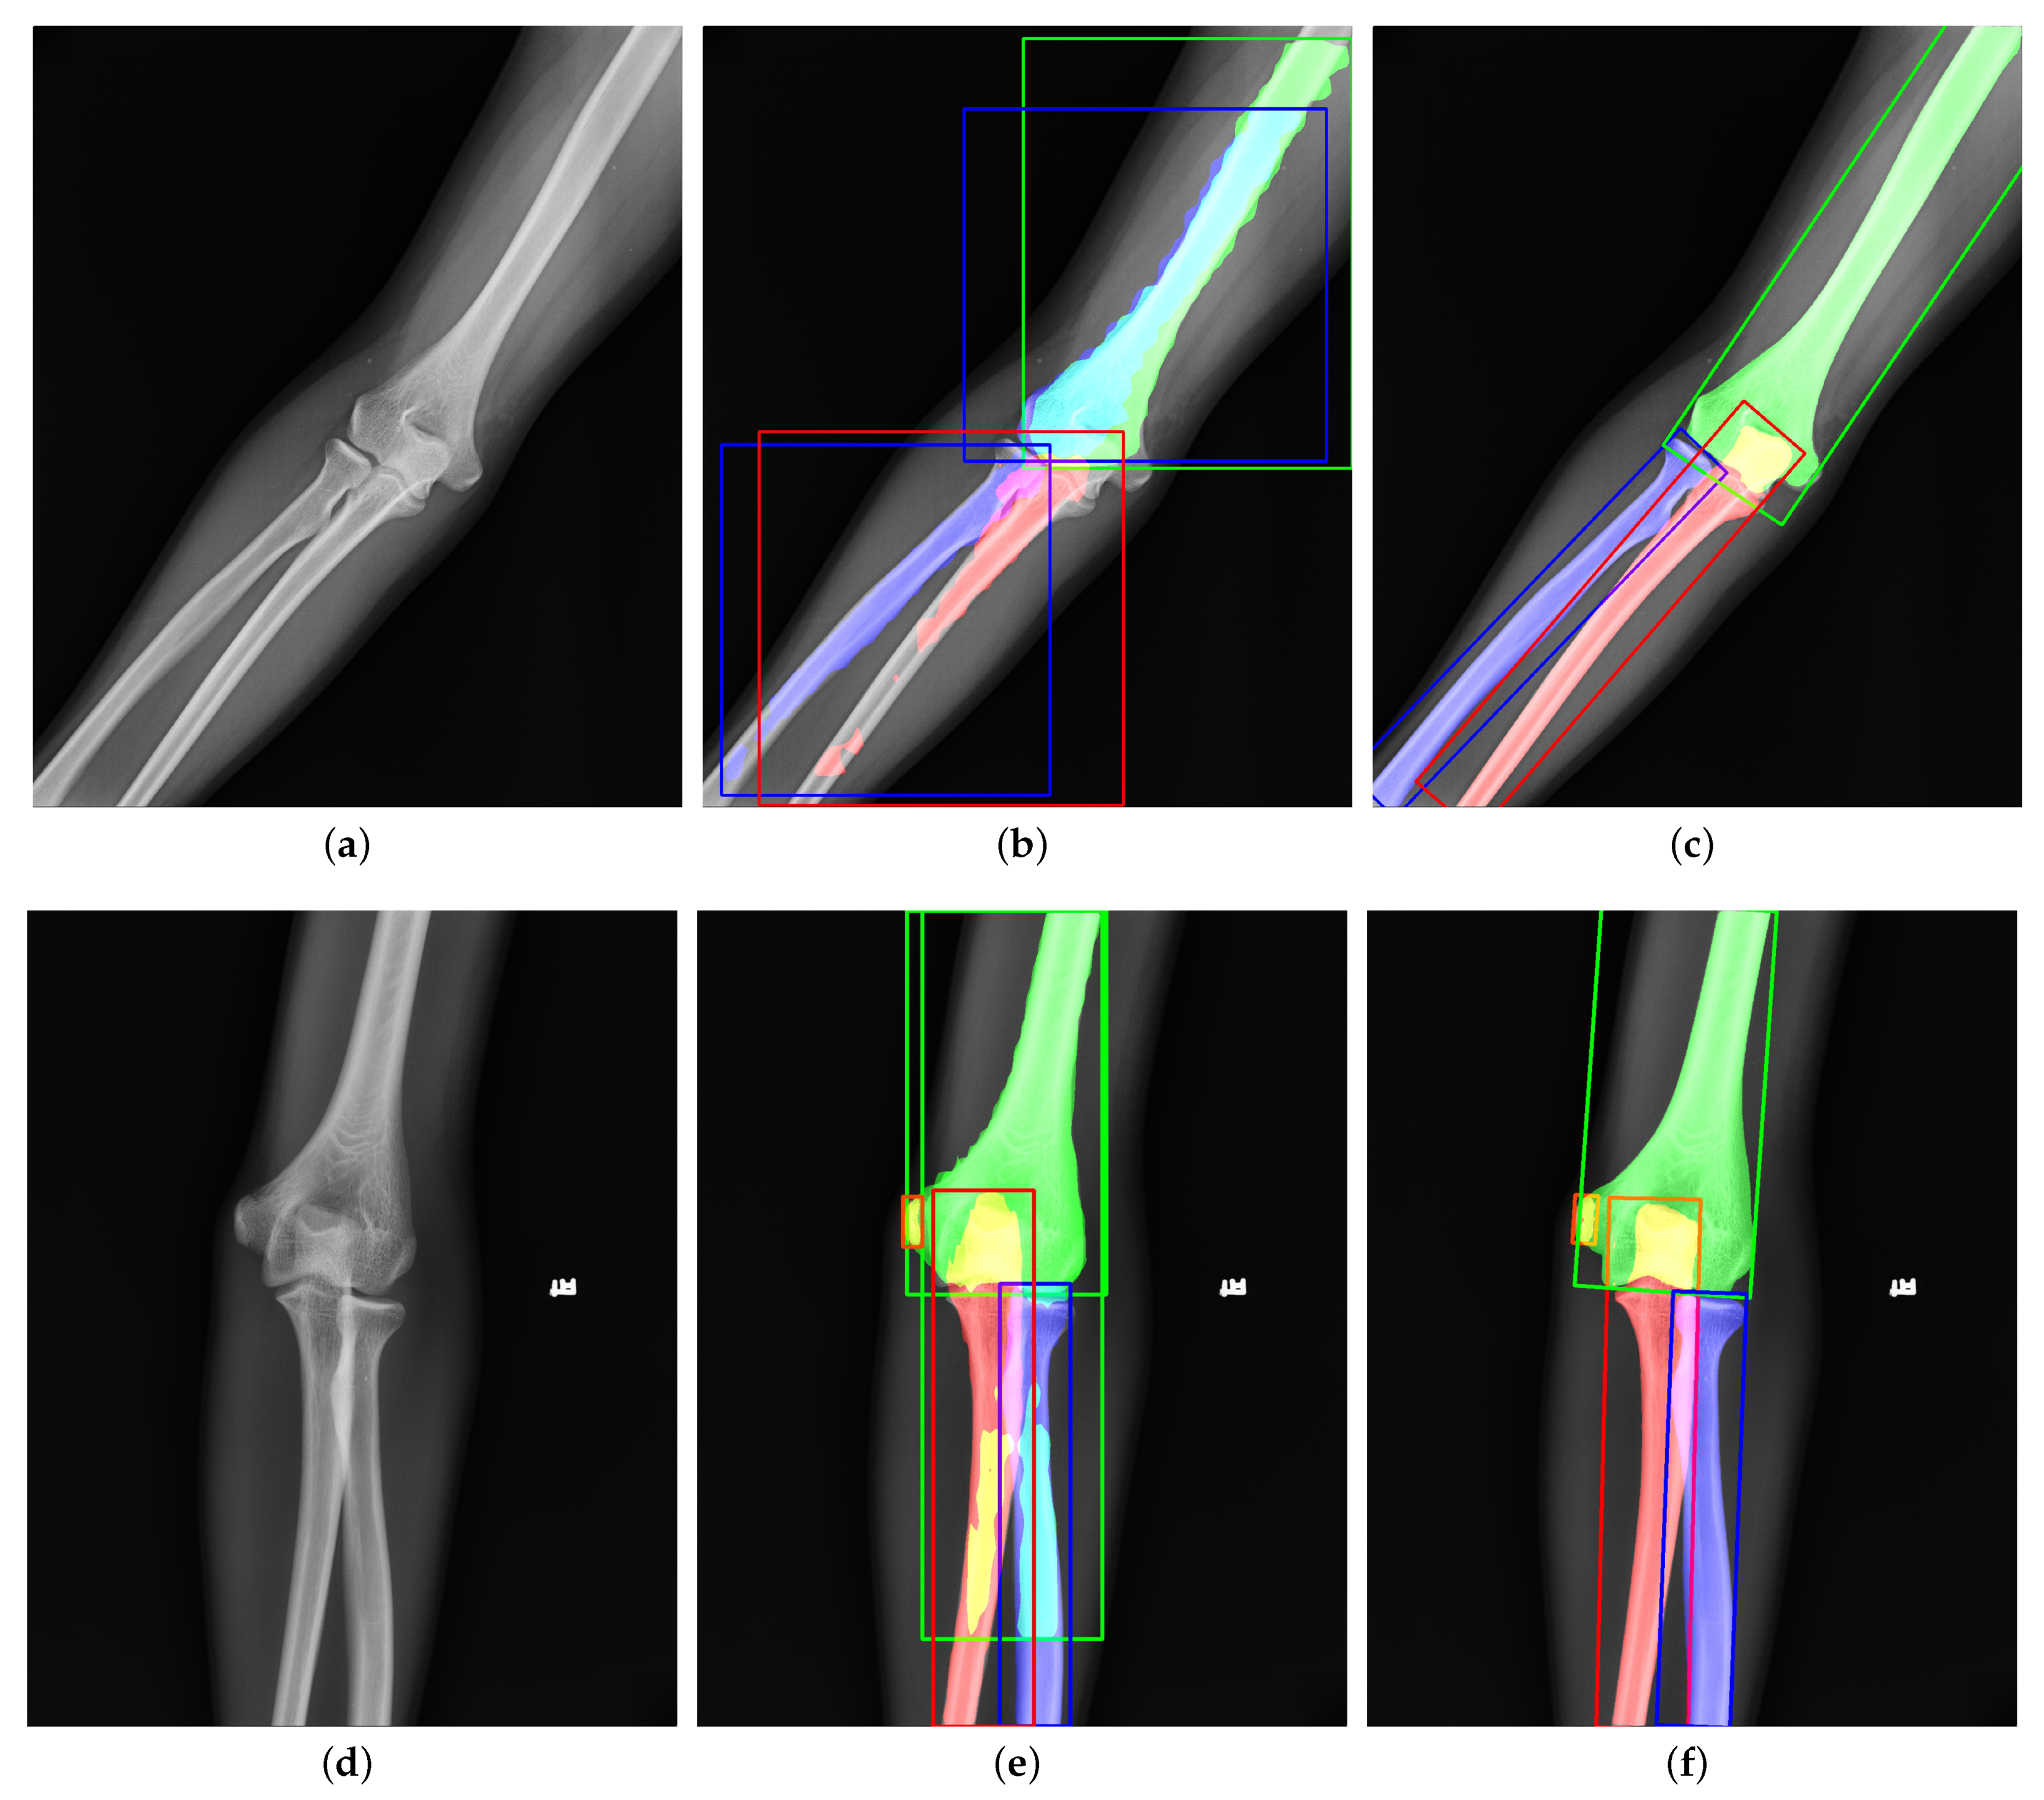

Instance segmentation is a DCNN-based method to generate the pixel-level segmentation mask with the specific category for each target in an image. As far as we know, we are the first to apply instance segmentation on the challenging task of extracting elbow bones. It is natural to take Mask R-CNN [12] as the instance segmentation algorithm. However, Figure 1b,e shows the poor results of edge extraction, bone localization, and bone classification, especially in the overlapping areas. There are three reasons for these results: (i) Mask R-CNN downsamples the original image by many times, and finally outputs a 28 × 28 binary image as the bone’s segmentation result. Directly upsampling the result to the original image will inevitably lose the bone’s edge information. (ii) Mask R-CNN uses the Horizontal Bounding Box (HBB) to provide a proposal region during pixel-level classification. The horizontal bounding box cannot fit the bones in any direction compactly. As shown in Figure 1b, when the angle between the bone and the horizontal direction is 45 , the bounding box probably contains contexts of other bones. The redundant information interferes with the bone segmentation results. (iii) Radiography causes overlapping between bones. Mask R-CNN uses four layers of convolution and upsampling to obtain bone segmentation results. Such a simple structure cannot cope with complex situations such as overlapping bones due to imaging principles. Furthermore, our method solves these problems and provides better results, as shown in Figure 1c,f.

Figure 1. Visualization of (a,d) original images, (b,e) outputs of Mask R-CNN [12], and (c,f) outputs of our proposed method. The green, red, blue, and orange represent the humerus, ulna, radius, and medial epicondyle, respectively. The overlapping regions are denoted by the addition of overlapping bones’ colors. Compared to Mask R-CNN, our results have better performance in bone edges and overlapping areas.